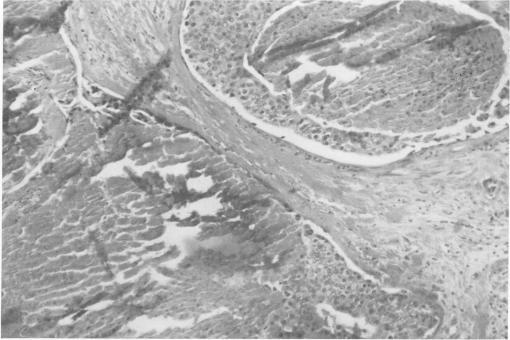

Management of nonpalpable breast carcinoma discovered by mammography.

Ann Surg. 1969 Sep;170(3):385-95. doi: 10.1097/00000658-196909010-00007.